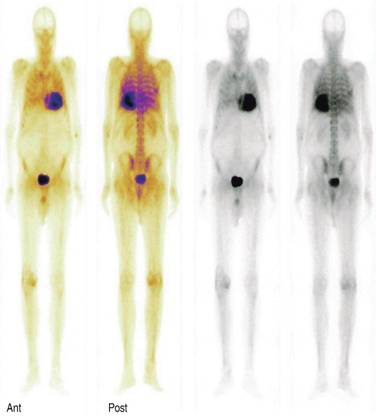

An old test with new diagnostic indications is a pyrophosphate or biphosphonate based bone scan commonly used to detect metastatic bone disease. Cardiac amyloidosis has been recognized by radionuclide since 30 years ago.27 The usefulness of bone scintigraphy scans in differentiating the most common AL and TTR cardiac amyloidosis with the phosphate based radionuclide 99m-Tc-3,3-diphosphono-1,2-propanodicarboxylic acid (99m-Tc-DPD) appeared more than 10 years ago.28

In bone scans we do not see cardiac uptake in normal hearts, that would be a Perugini uptake grade 0, when cardiac uptake is less than bone you say it is grade 1, uptake similar to bone is a grade 2, and when cardiac uptake is more than bone it is graded as 3 (Figure 5). Since several years ago it has been observed that in cardiac amyloidosis this type of bone scan discloses increased cardiac uptake of the radiotracer mainly in TTR amyloidosis, specifically the wild type TTR amyloidosis (WT-TTR). Several studies have clearly showed a sensitivity of more than 85% for WT-TTR and when we combine a positive cardiac uptake with a negative search for light chains in AL amyloidosis the sensitivity is practically a 100% for TTR amyloidosis. It is common practice to make a diagnosis of cardiac senile amyloidosis (WT-TTR) based exclusively on a positive grade 2 or 3 cardiac uptake of the bone radiotracer and a negative search for light chains in serum or urine. A false positive cardiac radiotracer uptake can be observed in AL cardiac amyloidosis, in such cases the cardiac bone scan radiotracer shows a mild grade 1 or 2 radiotracer uptake in one-third of patients with AL amyloidosis, however, these patients should have serological evidence of a monoclonal peak of light chain immunoglobulins.29 So with this information, it is possible to make the diagnosis of cardiac amyloidosis and specifically cardiac senile amyloidosis (WT-TTR) based on noninvasive test, obviating the need for a more invasive myocardial biopsy in this common frail population. Other important issue with phosphate based scans is the possibility to make early detection of cardiac involvement in ATTR, there is evidence of positive scans even before echocardiographic abnormalities are detected, an in addition 99m-Tc DPD has been compared with CMR for assessing cardiac amyloid infiltration and both methods are similar to identify myocardial amyloid infiltration, but the infiltration burden can be underestimated by visual analysis of CMR compared with 99m-Tc-DPD.30-35